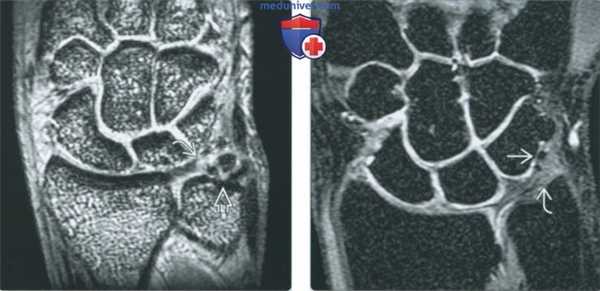

(Слева) Непрямая МР-артрография в режиме Т2 ВИ FS, коронарный срез: визуализируется травматический разрыв ТФХК, проявляющийся отрывом волокон от ямки и шиловидного отростка с появлением жидкости во влагалище сухожилия ЛРЗ.

(Справа) Непрямая МР-артрография в режиме Т2 ВИ FS, аксиальный срез, этот же пациент: на ладонной поверхности запястья определяется синовиальная киста в Отмечается наличие жидкости во влагалище сухожилия ЛРЗ. (Слева) Рентгеноскопия, передне-задняя проекция: визуализируется поступление контрастного препарата в ДЛЛС через центральную часть ТФХК, что свидетельствует о глубоком разрыве последнего.

(Справа) МР-артрография в режиме Т1ВИ FS, коронарный срез: наблюдается разрыв центральной мембранозной части ТФХД. Контрастный препарат распространяется в ДЛЛС. Дефект в данном месте обычно возникает вследствие дегенеративного процесса. (Слева) МР-артрография в режиме Т1ВИ FS, коронарный срез: отмечается, что распространение контрастного препарата ограничено лучезапястным суставом, а верхний край ТФХК имеет ровный контур. Пациент жалуется на боли с локтевой стороны запястья после падения.

(Справа) МР-артрография в режиме Т2ВИ FS, коронарный срез, этот же пациент: визуализируется неровный контур глубокого слоя ТФХК, обусловленный его разрывом. В ДЛЛС видна собственная жидкость, а не контрастный препарат, поскольку она характеризуется гипоинтенсивным сигналом на Т1 ВИ.